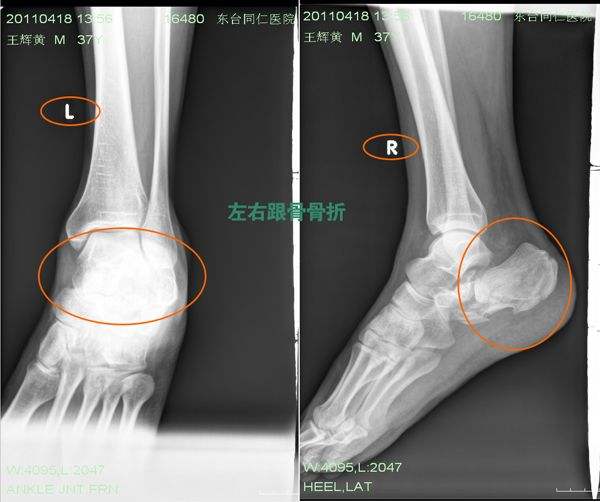

足跟跟骨骨折,要看程度,跟骨高度,宽度正常,没有特别移位的,关节面平整,有移位也不要超过1mm,可以先冰敷,控制肿胀后,打石膏,固定起来,脚趾头露出来!抬高下肢高于心脏!活动脚趾头,多抬腿,这样促进血液循环,利于消肿!

第二种情况,跟骨高度,宽度,关节面不正常,或者骨折片移位太明显,那么需要手术,手术后的的除了伤口需要换药,不用打石膏,可以马上进行锻炼,同时定时冰敷,可以防止减轻疼痛,防止僵硬,促进消肿,其他类似!抬高患肢和活动足趾,然后逐渐活动膝关节,然后活动踝关节,我认为是最重要的!也可以应用一些消肿的药物,快速消肿极为重要!